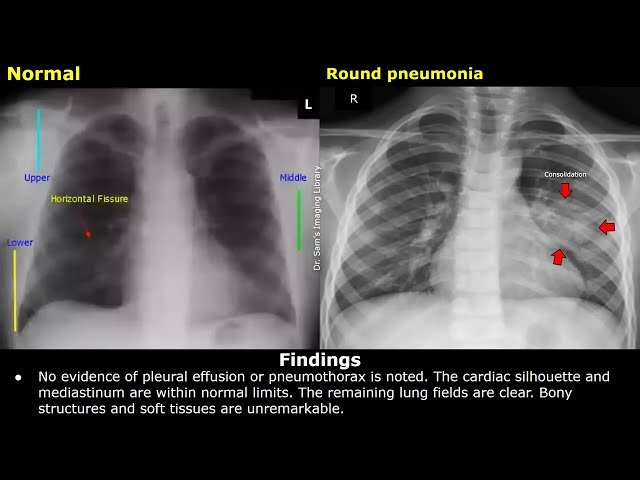

Master pneumonia diagnosis, treatment protocols, and chest X-ray interpretation through clinical case studies and medical lectures. Access expert-led content on YouTube from physicians and medical educators, covering pathophysiology, respiratory infections, and evidence-based management strategies for healthcare professionals and medical students.